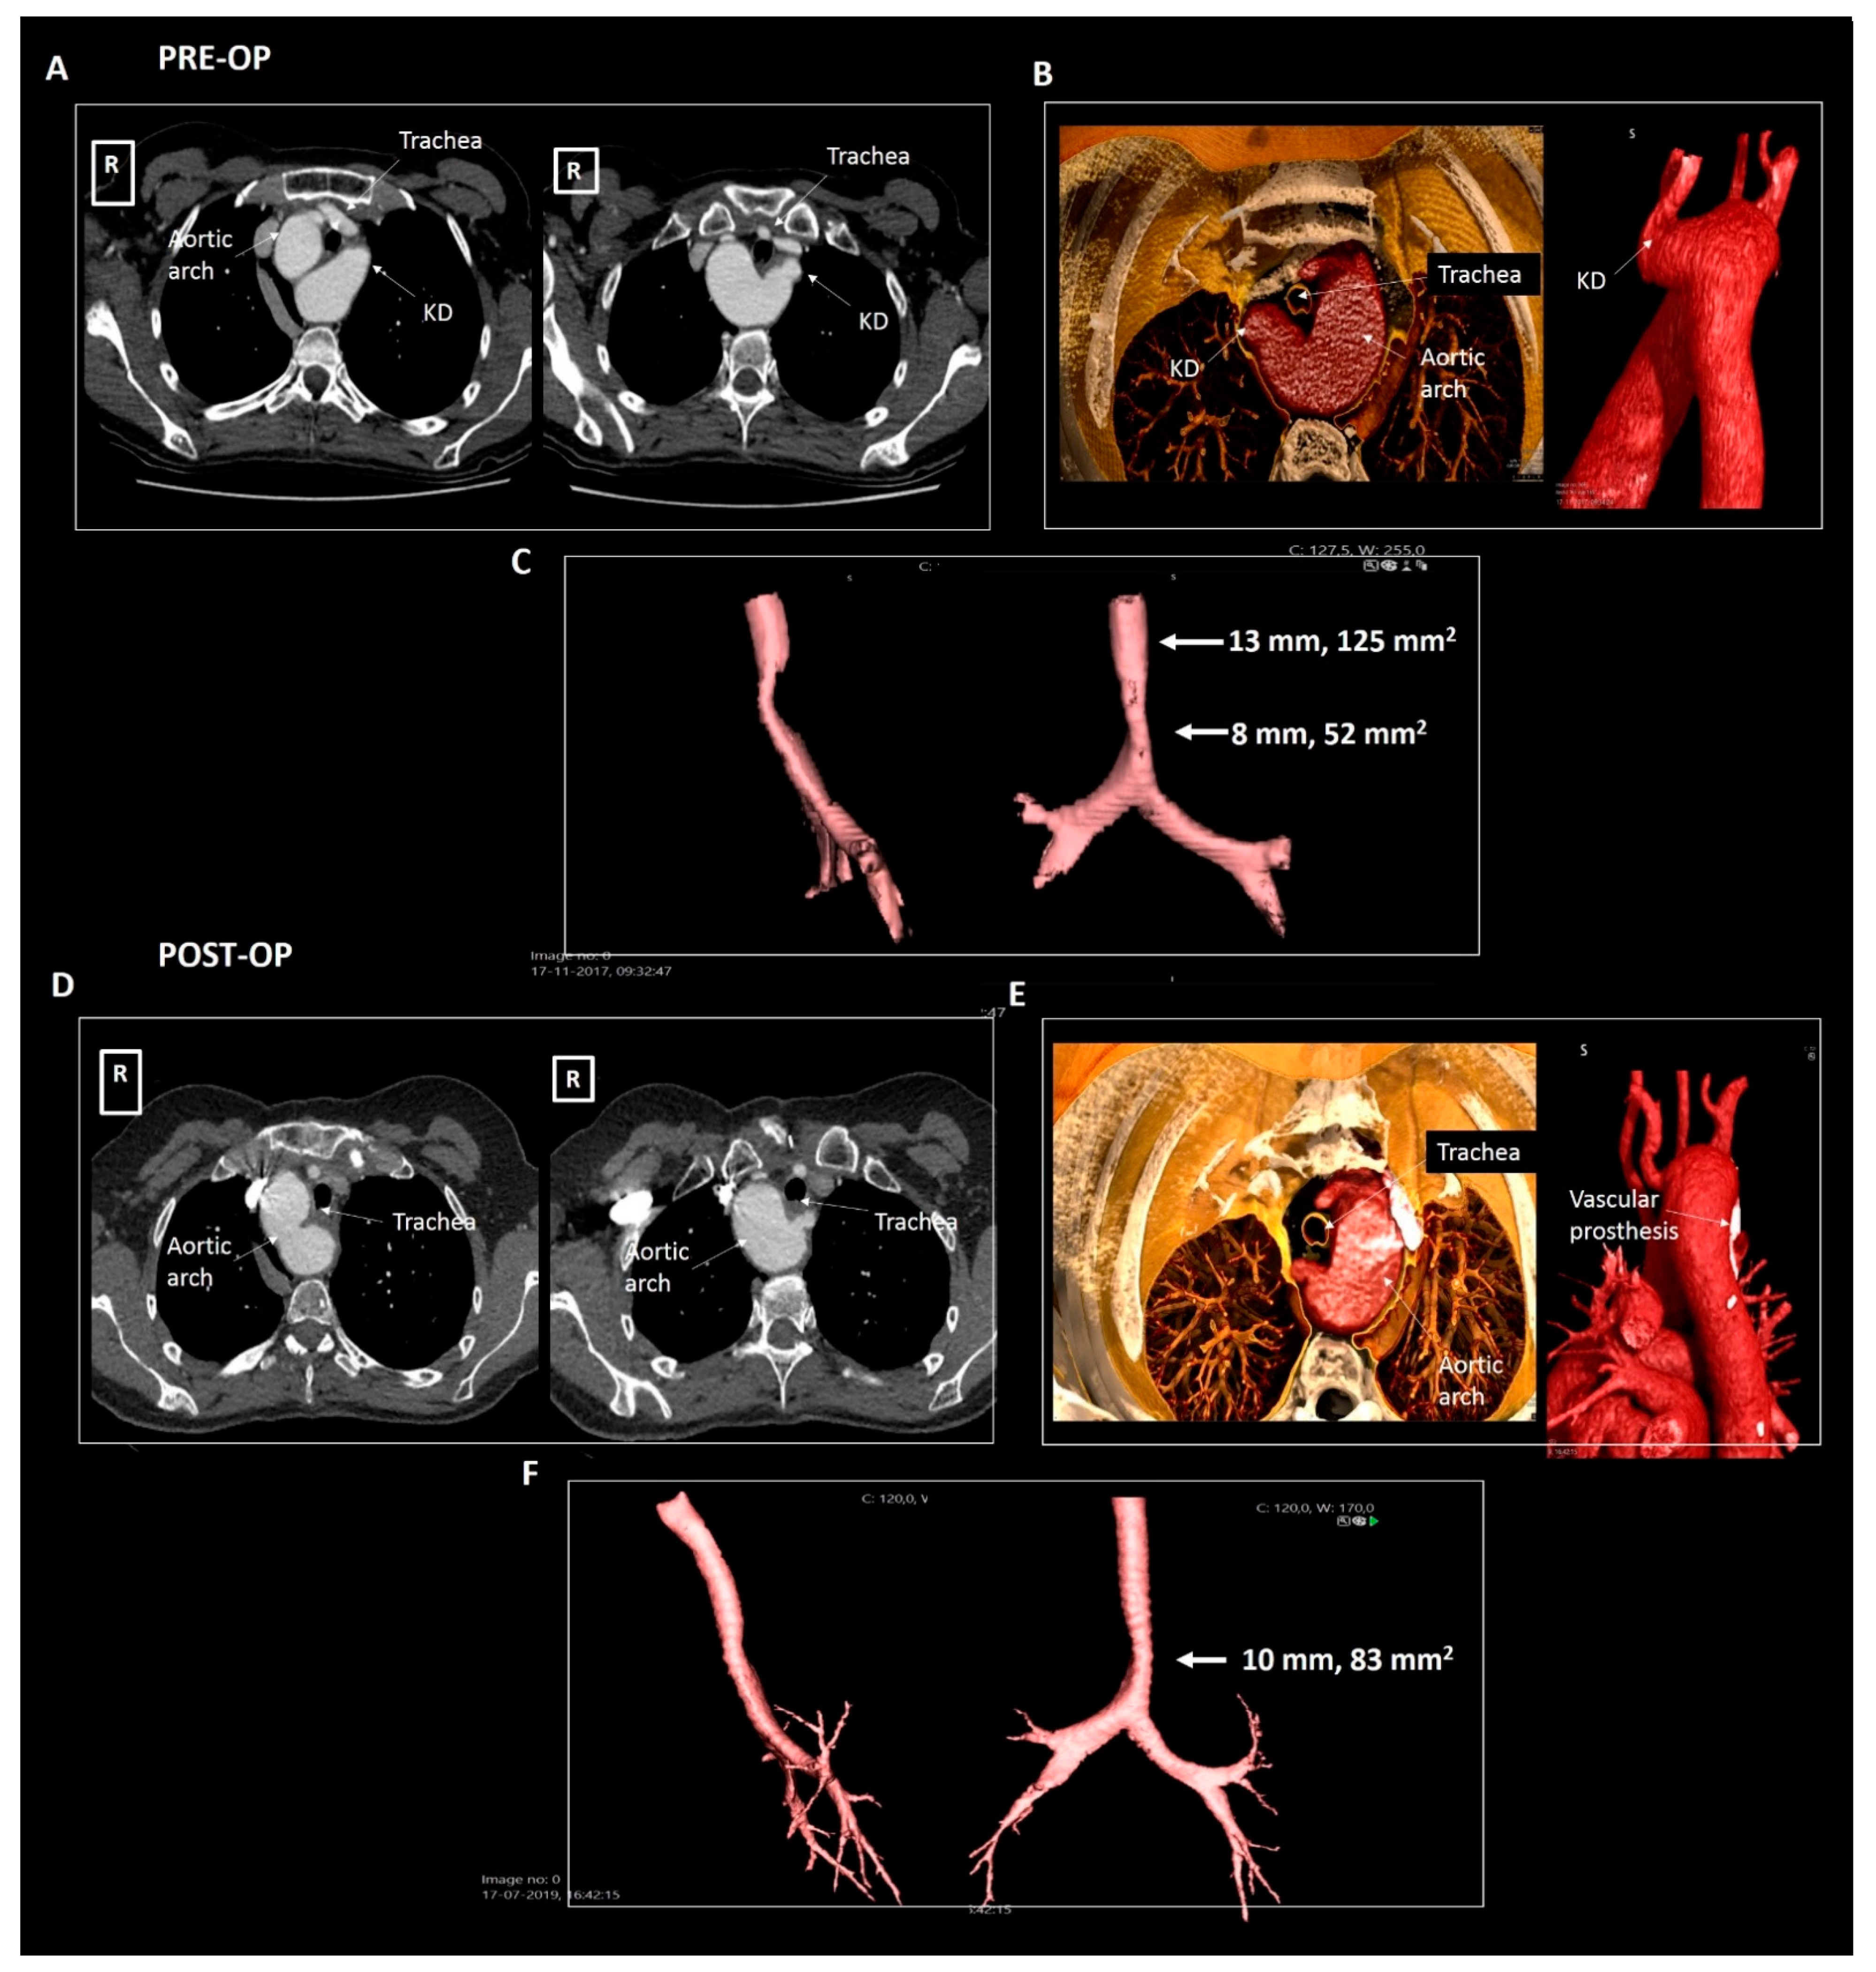

2.1. Patient 1

| Patient 3 | 50 | Female | Right-sided arch, aberrant LSA and KD | Symptomatic tracheal and esophageal compression | 30 × 29 mm, 870 mm2 | Dysphagia and dyspnea | Surgical resection |